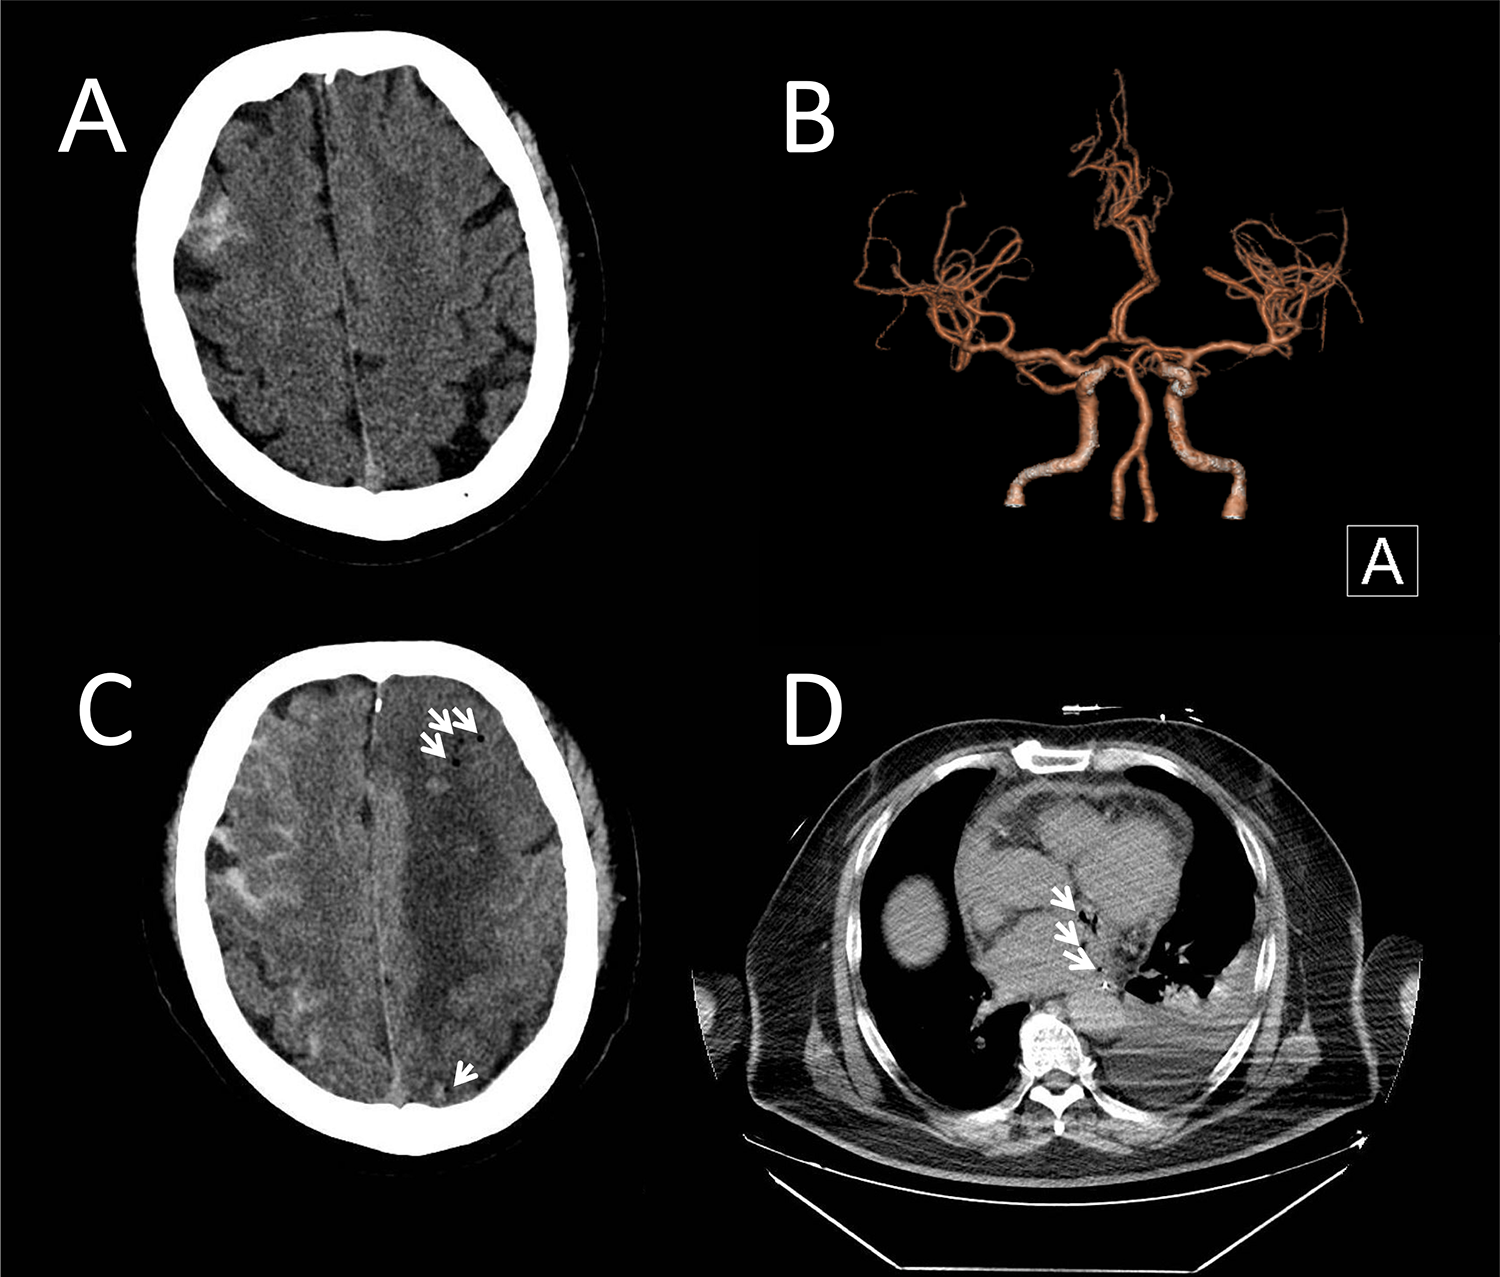

A 51-year-old male presented to our emergency department with fever and headache, three weeks after undergoing catheter ablation for atrial fibrillation. He had hypertension and diabetes for many years and took fosinopril and felodipine to lower blood pressure and acarbose to lower blood sugar. Atrial fibrillation was found 4 months ago. Rivaroxaban was taken for anticoagulation. Neurological examination on admission revealed disorientation and impaired calculation. Cranial CT and CT angiography showed right frontal SAH (Figure 1A) without evidence of an aneurysm (Figure 1B). Digital subtraction angiography (DSA) was not performed due to the small amount of early bleeding and the absence of evident aneurysm on initial CT angiography, as well as the patient's rapid clinical deterioration later. Chest CT revealed left pleural effusion and pericardial effusion. A lumbar puncture performed in the emergency department on the same day showed an opening pressure of 225 mmH2O. Cerebrospinal fluid (CSF) analysis revealed a nucleated cell count of 103 mm3 (13% mononuclear cells, 87% polymorphonuclear cells), a protein level of 0.45 g/L, glucose of 4.85 mmol/L, and chloride of 125.4 mmol/L. No bacteria, fungi, acid-fast bacilli, or cryptococci were detected on smear. For the central nervous system infection with unidentified pathogens, meropenem and acyclovir were administered. For the subarachnoid hemorrhage and intracranial hypertension, nimodipine and mannitol were initiated, along with blood pressure control. Anticoagulants were discontinued due to suspected infective endocarditis and the presence of intracranial hemorrhage. The next day, the patient remained febrile with headache, and inflammatory markers and cardiac enzymes showed progressive elevation. Neurological examination indicated that the patient was drowsy. CSF analysis via Next-generation sequencing (NGS) identified elevated levels of Prevotella nanceiensis. Minocycline and vancomycin were added to the antibiotic regimen, and acyclovir was discontinued. However, the next following day, the patient was in a mild coma. Repeated cranial CT showed increased SAH, with air signals and infarcts (Figure 1C). Repeated chest CT showed air signals in the left atrium and around (Figure 1D). Blood NGS confirmed bacteremia, identifying common Gram-positive and Gram-negative bacteria typically found in the oral cavity. Echocardiography indicated the presence of a neoplasm in the left atrium, with significant oscillation during the cardiac cycle, and partial movement into the left ventricle during diastole via the mitral valve. Gastroscopy confirmed the presence of an AEF. Considering the high surgical risk and family's wishes, conservative treatment was chosen over surgery. The patient died 17 days after admission due to sepsis and infective endocarditis. The detailed development of the disease can be seen in Figure 2.

Brain CT and chest CT of the patient. (A) Initial cranial computed tomography (CT) revealed a right frontal subarachnoid hemorrhage. (B) CT angiography ruled out aneurysms. (C) Repeated cranial CT showed increased SAH, with air signals (arrows), infarcts and hemorrhagic densities in the left hemisphere. (D) Chest CT showed air signals (arrows) within and around the left atrium.

In this case, we speculated that a microaneurysm had formed due to bacteremia, leading to SAH and initially presenting with fever and headache. Prevotella nanceiensis is one of the core anaerobic species in the oral microbiome (5). We inferred that bacteremia from oral flora (e.g., Prevotella spp.) may promote infectious aneurysm formation via endothelial inflammation, potentially explaining SAH in AEF-related sepsis (6). Both blood and CSF NGS results further supported the presence of bacteremia and the potential formation and rupture of an aneurysm. Clinicians initially considered infective endocarditis and initiated active treatment but did not recognize that AEF had already developed. As the patient's condition deteriorated, repeated brain and chest CT scans revealed intracranial air, ultimately identifying the true etiology. The sequential occurrence of subarachnoid hemorrhage (SAH) and air embolism reflects an evolving pathophysiology: Sepsis initially triggered the formation and rupture of an infectious intracranial microaneurysm, causing SAH. The infection-induced vascular injury disrupted the blood-brain barrier. Subsequent enlargement of fistulous tracts permitted progressive air entry. As demonstrated in Figure 1C, bilateral hemispheric involvement was observed: the right hemisphere showed predominant SAH, while the left exhibited more pronounced infarction, parenchymal hemorrhage, and air densities. The involvement of non-contiguous vascular territories across both hemispheres further supports the possibility of cardiogenic embolism.